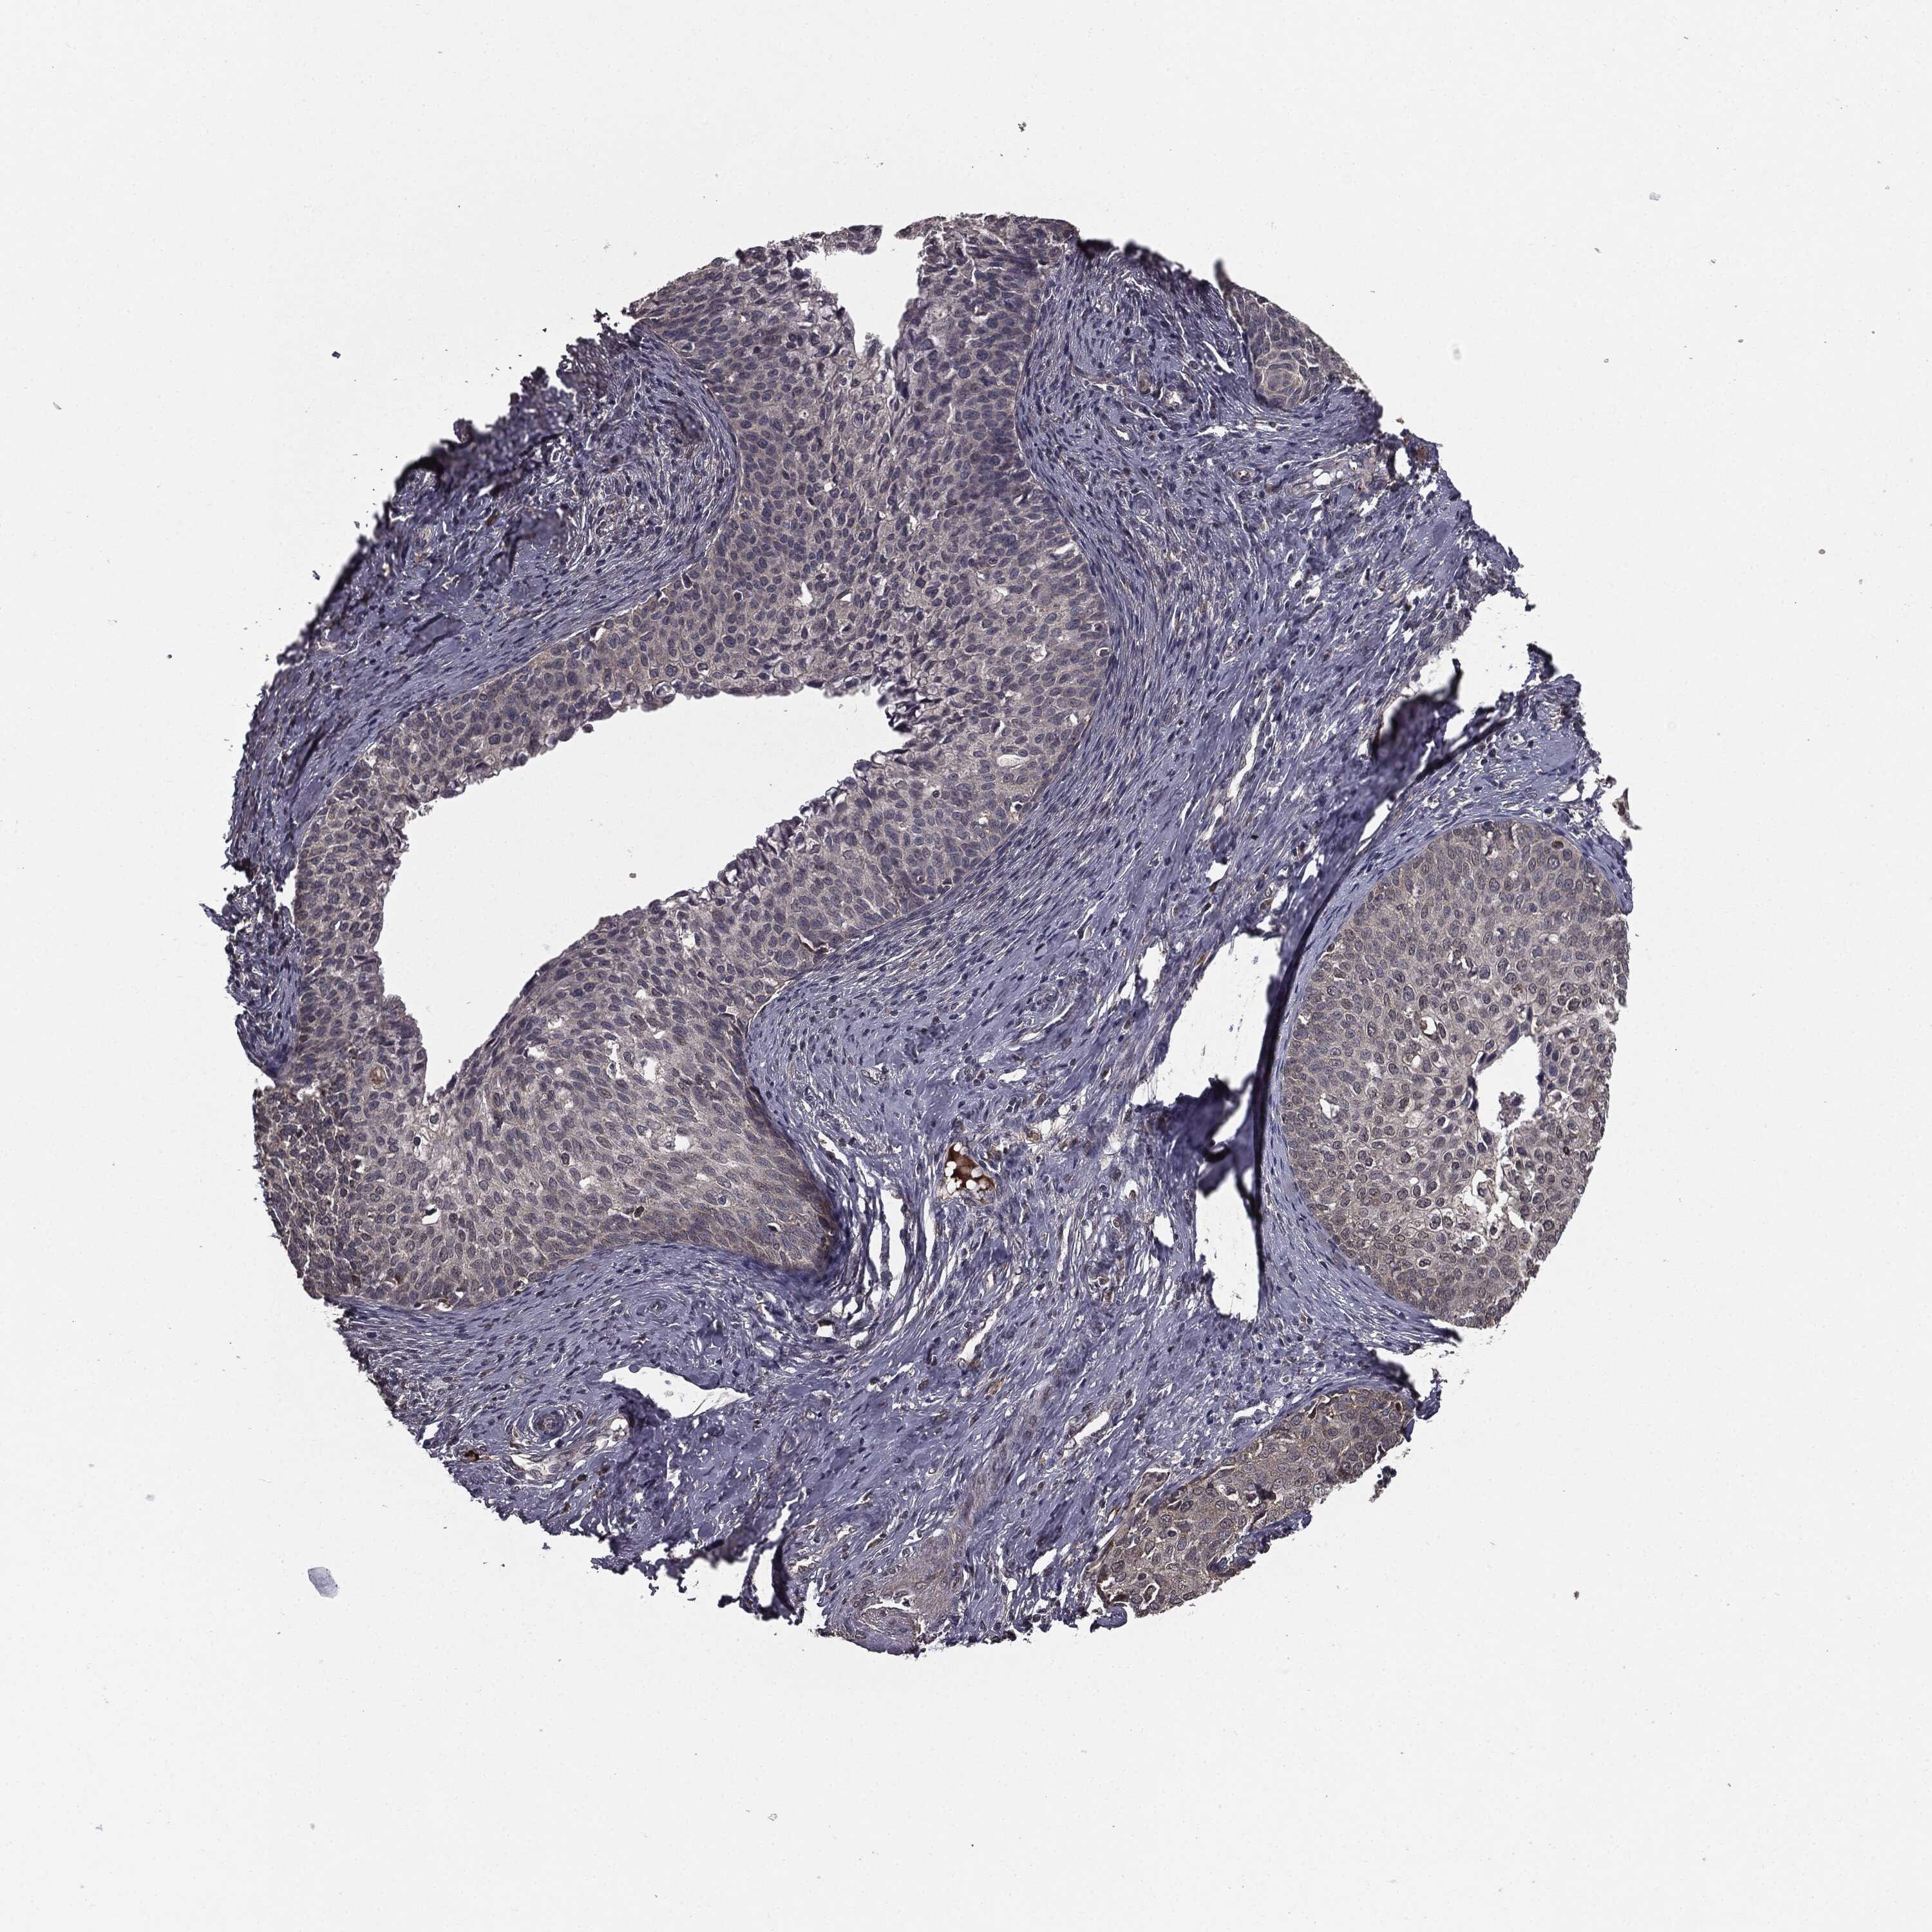

CERVICAL CANCER - Protein expressioni

A mouse-over function shows sample information and annotation data. Click on an image to view it in a full screen mode. Samples can be filtered based on level of antibody staining by selecting one or several of the following categories: high, medium, low and not detected. The assay and annotation is described here.

Note that samples used for immunohistochemistry by the Human Protein Atlas do not correspond to samples in the TCGA dataset.

Antibody stainingi

Antibody staining in the annotated cell types in the current human tissue is reported as not detected, low, medium, or high, based on conventional immunohistochemistry profiling in selected tissues. This score is based on the combination of the staining intensity and fraction of stained cells.

Each image is clickable and will lead to virtual microscopy that enables deeper exploration of all samples and also displays staining intensity scores, fraction scores and subcellular localization as well as patient and tissue information for each sample.

Antibody HPA052606

Antibody HPA077139

Staining

High

Medium

Low

Not detected

Intensity

Strong

Moderate

Weak

Negative

Quantity

>75%

75%-25%

<25%

None

Location

Nuclear

Cytoplasmic/membranous

Cytoplasmic/membranous,nuclear

Squamous cell carcinoma, NOS

Adenocarcinoma, NOS